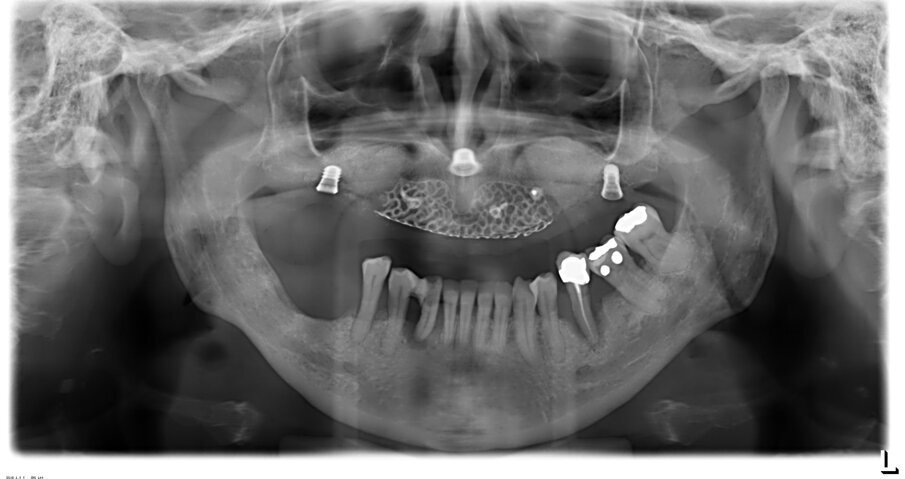

Inoltre da questa nuova ceratura dobbiamo ricavare una protesi radiografica con i punti di repere radiopachi che ci servirà per fare il matching con i nuovi file DICOM dell’osso rigenerato (Figg. 35, 36). Fatte le opportune verifiche nel software di chirurgia guidata, si pianifica l’intervento di posizionamento implantare (Figg. 37-40). Si programma lo stesso giorno della chirurgia anche il carico immediato degli impianti; decisione supportata dalla verifica istologica dell’osso rigenerato che dovrà comunque essere confermata il giorno del posizionamento implantare durante il quale si misurerà il torque di inserimento degli impianti e la stabilità primaria con il sistema OSSTELL mentor (Integration Diagnostics) che sfrutta l’analisi della frequenza di risonanza.

Grazie al flusso digitale, possiamo inserie nel software anche il file STL del provvisorio pre-chirurgico preparato e quindi progettare il provvisorio immediato (Fig. 41). La pianificazione degli impianti a questo punto viene effettuata in modo protesicamente guidato ed è facile posizionare correttamente l’impianto e verificarlo nelle cross del software. Si progetta e si disegna quindi la dima chirurgica (Fig. 42). Il giorno dell’intervento abbiamo già tutto pronto e la paziente presenta uno stato di salute dei tessuti ottimale grazie anche al fatto che ha potuto portare per tutto il periodo una protesi fissa.

Procediamo quindi all’inserimento di sei impianti BLX Straumann (Straumann Group) (Fig. 43, 44), ed utilizziamo gli impianti posizionati nella tuberosità per stabilizzare la dima chirurgica e il provvisorio sul modello master di lavoro digitale. La funzionalizzazione del provvisorio immediato subito dopo l’intervento viene effettuata con l’utilizzo della tecnica DIL19 (Figg. 45, 46).